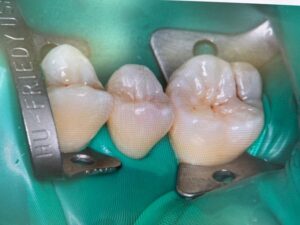

ラバーダム

三鷹院ではその欠点をカバーするために、被せ物や根管治療をする際はラバーダムやzooといった湿度を除去してくれる器具を多く採用しております。

このように歯をラップしてくれることで唾液や口腔内の湿度をシャットアウトして良い治療ができるように日々努めております。